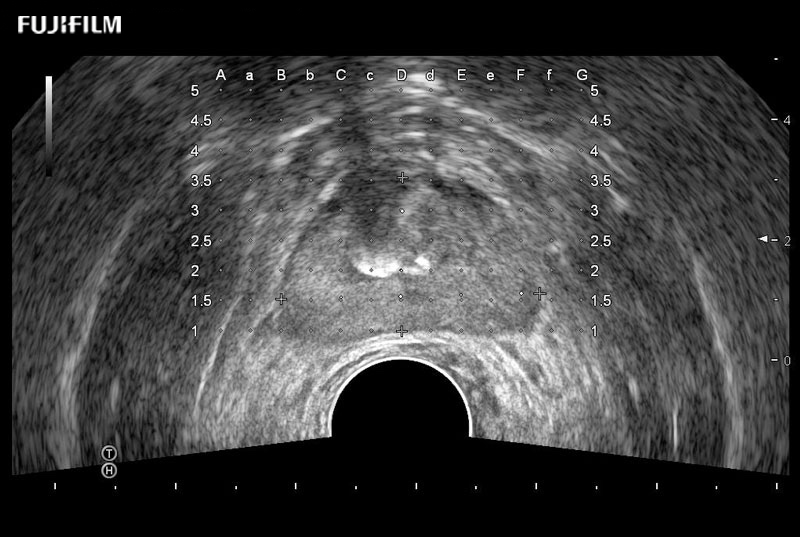

Ideal transducer for Transperineal Biopsy, Hydrogel Spacer Placement, Brachy LDR & HDR, Cryo, and MPMRI procedures.

Exclusive 200° FOV end-fire prostate biopsy transducer.

Provides real-time imaging of both the sagittal and transverse planes